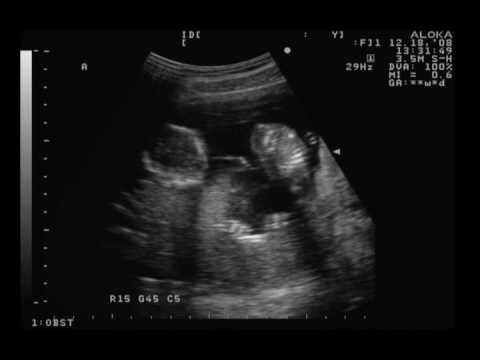

15 Weeks Pregnant Ultrasound Amie S Castle 15 Weeks Pregnant

Week 15 Pregnancy Ultrasound Fetus Development And Symptoms

What To Expect In Ultrasound Done At 15 Weeks Pregnant New Kids Center